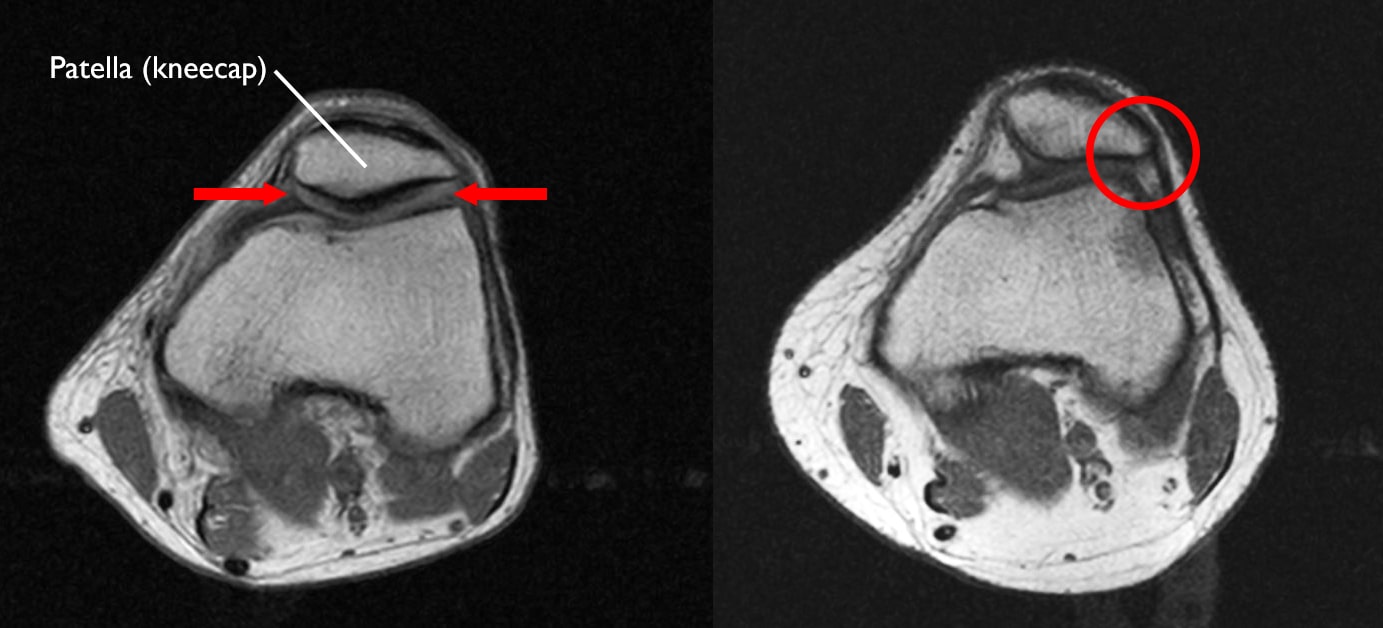

Patellofemoral pain syndrome can also be caused by abnormal tracking of the kneecap in the trochlear groove. In this condition, the patella is pushed out to one side of the groove when the knee is bent. This abnormality may cause increased pressure between the back of the patella and the trochlea, irritating soft tissues.

normal knee and knee of of alignment

(Left) In this MRI scan, the kneecap is normally aligned within the trochlear groove (arrows). (Right) Here, the kneecap has shifted out of the groove and is pulled toward the outside of the leg (circle).

Images courtesy of Stuart J. Fischer, MD, FAAOS